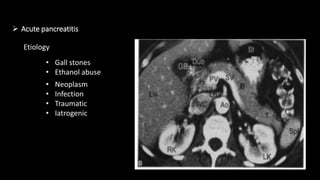

 Acute pancreatitis

Etiology

• Gall stones

• Ethanol abuse

• Neoplasm

• Infection

• Traumatic

• Iatrogenic